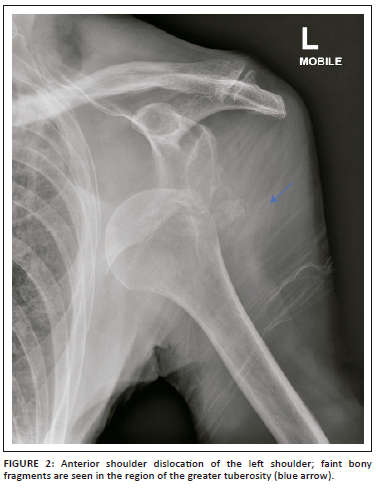

Control plain radiographs are mandatory. Three views must be obtained (anteroposterior, axillary view and lateral view) to confirm the reduction and rule out bony compression fractures of the humeral head (Hill-Sachs lesion), push-off fractures of the glenoid (bony Bankart lesion), bony erosions (glenoid bone loss) or to identify fractures that were initially not visible (Figure 2, Figure 3, Figure 4 and Figure 5). Kahn and Mehta reported a rate of 37.5% of fractures which were visible only on post-reduction radiographs.15